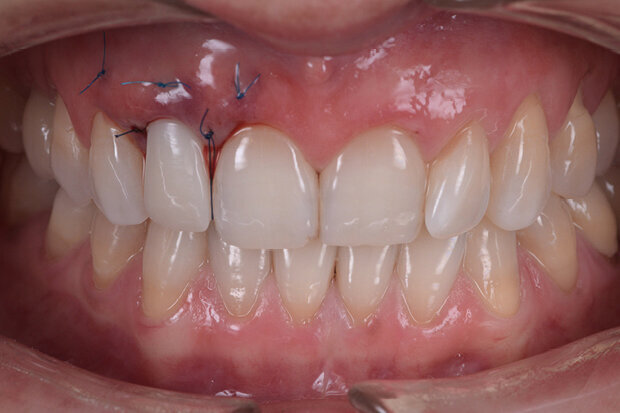

Fig. 15. Close-up of the final situation

This method ensures the accuracy of the restoration procedure. The transgingival areas have already been formed at the time of the temporary restoration. In the present case, the thickness of the gingival tissue should be additionally increased. For the final restoration, a Ti base of the same length as the one for the temporary restoration is used. This time, however, the base features an anti-rotation lock. A large selection of materials is available for the final restoration. We normally use hybrid restorations for the restoration of single implants. Here, the restoration consists of a monolithic zirconium oxide abutment (Zenostar) and a monolithic multi-shaded all-ceramic crown (IPS e.max ZirCAD MT Multi). The restoration is characterized with stains and completed without any shape modifications (Figs 14 to 16).